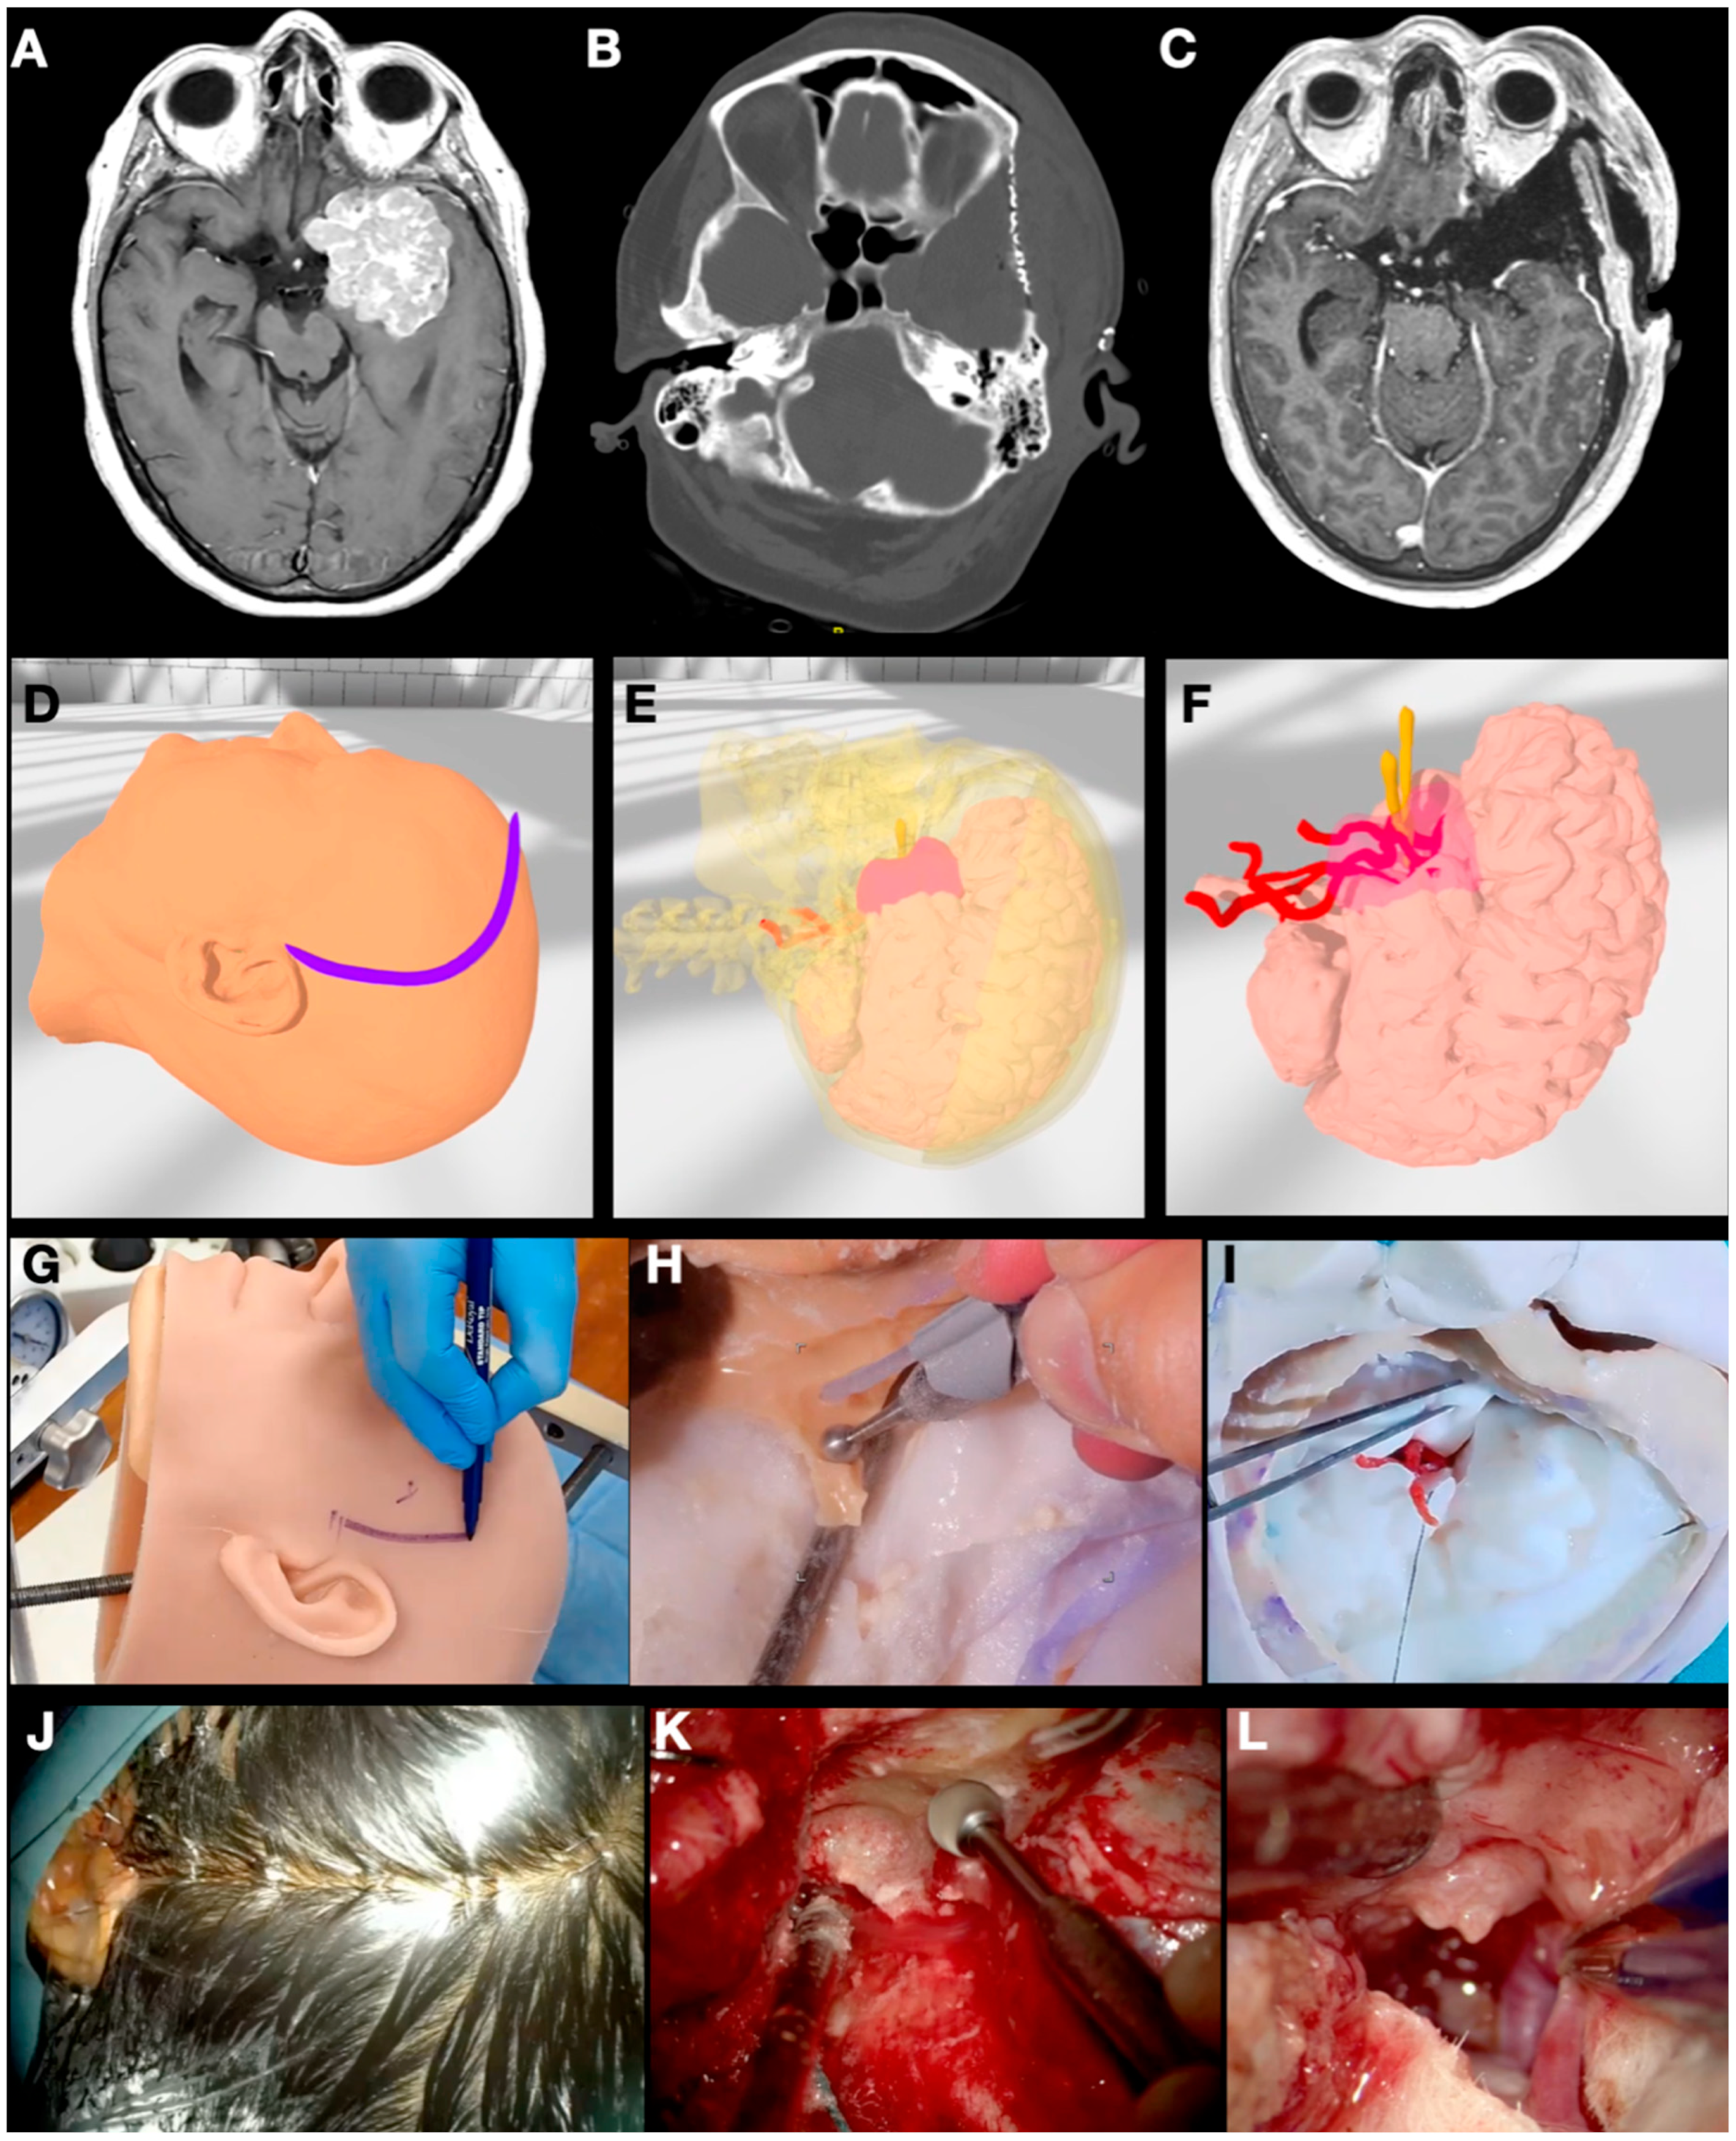

3.1. Case 1: Sphenoid Wing Meningioma